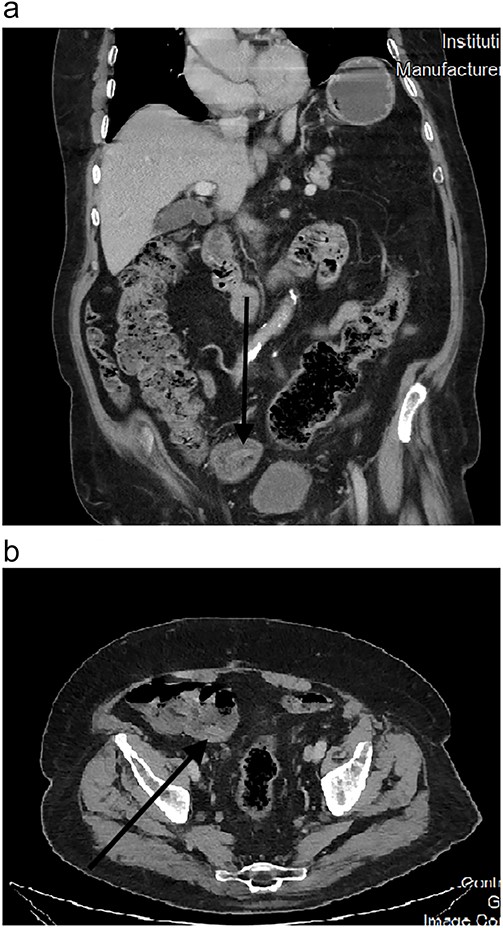

CT scans also picked up this anomaly as early as 2010 (Fig. 2). Further scans in the following years showed no change in morphology (Fig. 3a and b), and it was kept under surveillance. To note, our patient did not have any abdominal symptoms suggestive of appendiceal origin throughout the years.

Endoscopically, it appears as a tubular elongated polypoid structure arising from the appendiceal orifice [11, 12]. Endoscopists can be reluctant to rule out neoplastic findings without a histological confirmation (such was the case in our patient’s 2012 colonoscopy). On CT scans, it appears as an elongated structure with a layered appearance at the appendiceal orifice. The presence of feces in the cecum might make diagnosis difficult [13].